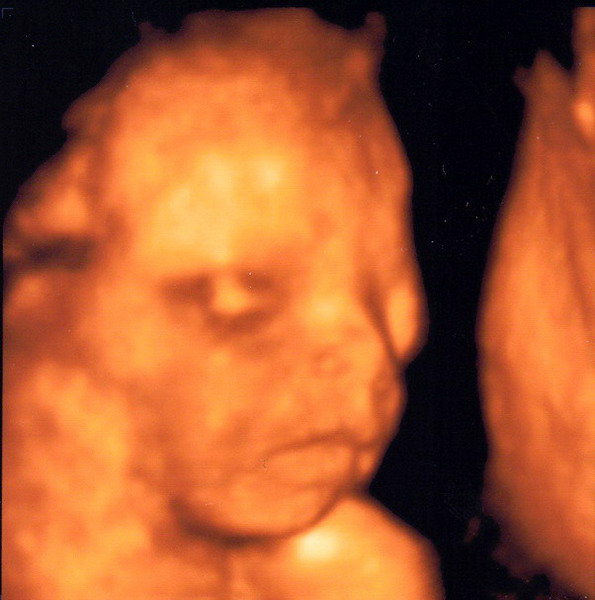

mintha apró rúgások lennének, de érezni hogy azért más, finomabb mozdulat mint egy rúgás, és teljesen ritmikusan ismétlődik egy darabig aztán elmúlik

Olyan van még, amit én kúszásnak nevezek, azaz jön egy kis dudor (általában a lába, fent a köldökömnél) és az szépen végighalad, kúszik a hasam egyik oldaláról a másikba, majd eltűnik (=visszahúzza..?)...